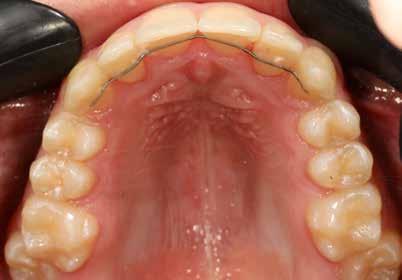

Minden fogszabályozó kezelés után nagyon fontos a retenció, de ilyen eltérés esetén különösen, mivel a recidíva veszély nyitott harapás esetén a legnagyobb. A fogak és a harapás megtartása fix és kivehető retainer-ekkel történik.

A kivehető helyben-tartók legfontosabb eleme a mindkét fogívet összekötő ún. Splint (19. kép), amely egyrészt saggitálisan tartja a helyén a mandibulát, hogy ne csússzon vissza hátrafelé, másrészt segít a harapás zártan tartásában a növekedés teljes befejeződéséig.